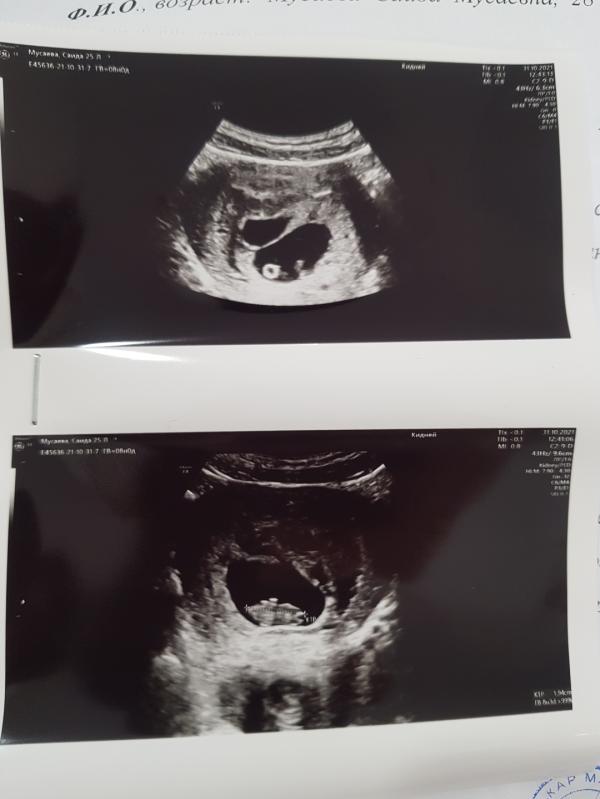

Всем приветик. У меня вопрос, может было у кого так же. На первой узи 5недель было видно одно плодное яйцо. На 2й узи 8нед в этом же яйце уже был виден эмбриончик , но появилось рядом еще одно плодное яйцо только пустое. Что это значит? Этот вопрос на данный момент мне не дает покоя...

У меня было 2 плодных яйца. Была подсадка двух эмбрионов.

Но второй эмбрион не прижился. И потом, как мне объяснили, из этого плодного яйца образовалась гематома. При чём за 2 недели. Которая дала кровотечение на 9 недели. В итоге лежу, покой. И жду когда рассосётся.